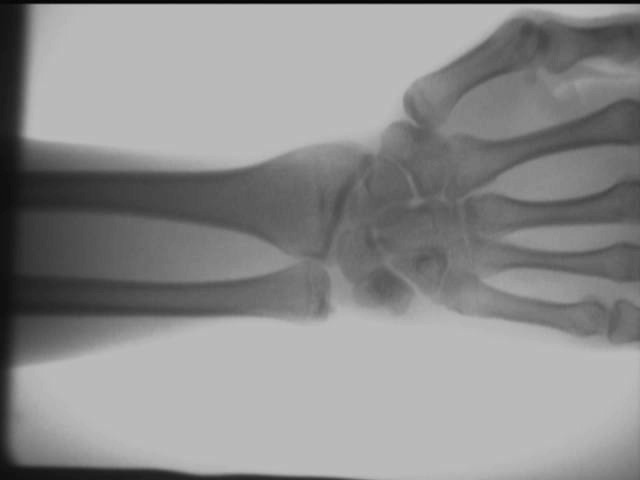

Diagrama de efeito de teste no local do detector de raios X ortopédico

Efeito de perspectiva da palma

Os resultados dos testes acima são obtidos no local usando um AS-C200máquina de raio X portátil